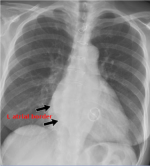

| F | Fields Fissures FB | • masses, consolidation, vessels, bronchograms • ?fluid in fissures, change of position • FB's- ETT, CVC, NG tubes, other |

| H | Hilar mediastinum | • LNs, Ca++, masses • widening - suggestion of dissection • displacement - suggestion of mass • angle of main bronchi - suggestive of collapse, masses • L hilum should NEVER be lower than R |